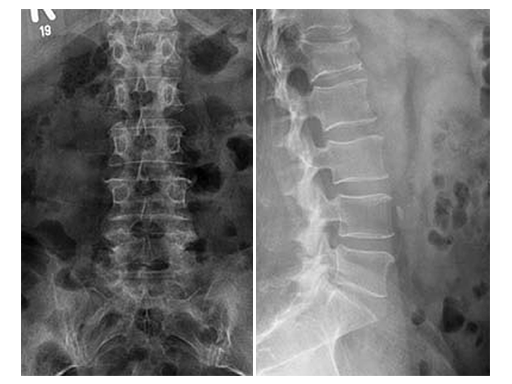

Preoperative analysis

X-rays and CT scans were performed for preoperative analysis, definition of the fracture type and surgical pre-op planning.

The lateral x-ray and CT scans showed a typical wedge deformity of the fractured vertebral body (L1). The fracture included the cranial endplate as well as the anterior and posterior wall.